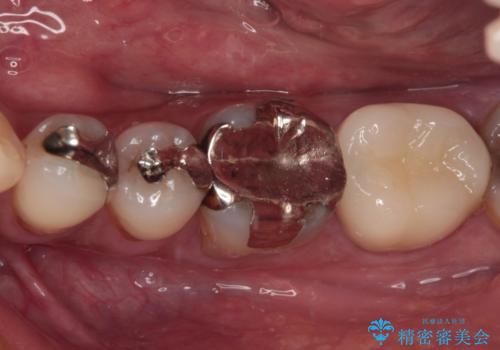

- 痛みを感じ近医を受診したものの、違和感が改善しないとのことで来院された患者様です。

診査をしたところ、神経組織に炎症及ぼすような大きなむし歯があることが分かりました。

虫歯が歯髄腔(神経の部屋)に達している可能性が非常に高かったため、炎症を起こしている神経組織を部分的に切除し、歯根部分の神経組織を保存する治療法が望ましいと考えられました。

歯質の欠損が大きいため、処置後はオールセラミッククラウンにて補綴治療を行うこととしました。